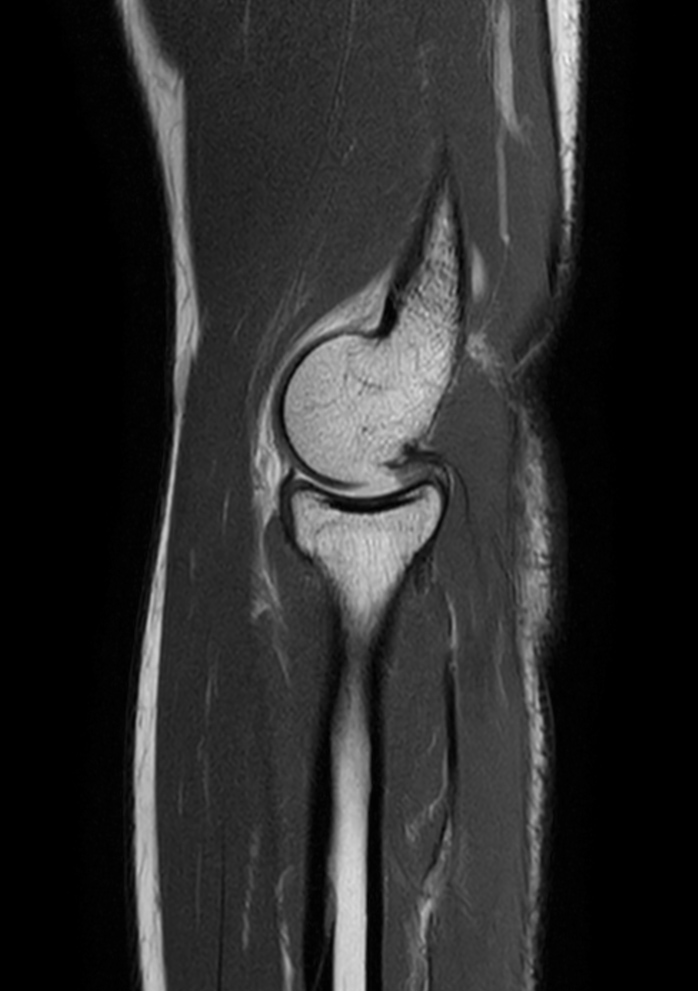

High quality Elbow imaging with Compressed SENSE

Spital Uster, Switzerland